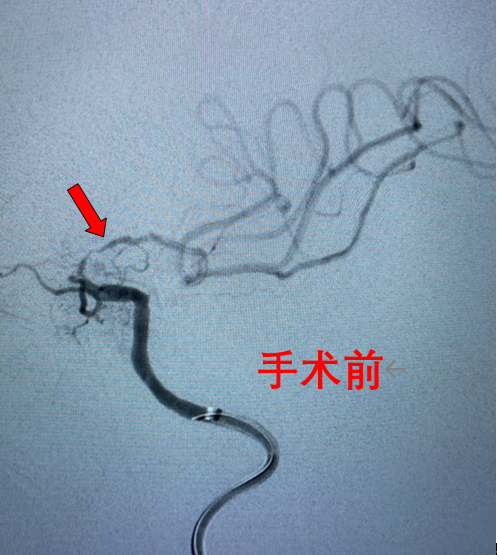

随着时间的推移,陈大爷病情不断加重,突然有一天他失去了意识,家人赶紧将他送到了自贡四院神经内科救治。经过专家的检查和诊断,陈大爷的病因找到了——左侧颈内动脉末段堵塞,导致了我们大家熟知的脑梗。

要解决陈大爷的问题,除了规范的药物治疗外,通过介入手术治疗的方式可能会达到更好的治疗效果。

做好术前准备后,陈大爷进入介入手术室,神经内科医务人员成功为其完成了“左侧颈内动脉末段血管成形、支架植入术”。

术后,陈大爷头晕、行走不稳等症状消失,恢复到正常状态。